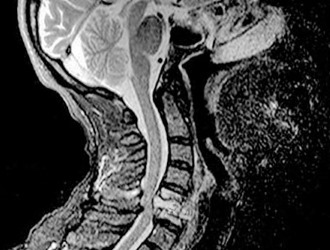

Магнитно-резонансная томография (МРТ) шейного отдела позвоночника является высокотехнологичным методом диагностики, использующим магнитные поля и радиоволны для получения изображений структуры костной ткани и окружающих ее мягких тканей, включая костный мозг, без необходимости хирургического вмешательства.

Эта методика также позволяет оценить кровоток в области шеи и головы.

МРТ шейного отдела позвоночника является важным диагностическим инструментом, который позволяет врачам получить детализированное изображение структур шеи, включая позвонки, межпозвоночные диски и мягкие ткани. Специалисты отмечают, что этот метод особенно полезен для выявления различных заболеваний, таких как остеохондроз, грыжи дисков и воспалительные процессы. Процедура проводится безболезненно и не требует специальной подготовки. Пациенту необходимо лечь на стол аппарата, который затем перемещается в магнитное поле. Врачи подчеркивают, что МРТ не использует ионизирующее излучение, что делает его безопасным для большинства пациентов. Результаты исследования помогают врачам точно установить диагноз и выбрать оптимальный план лечения.